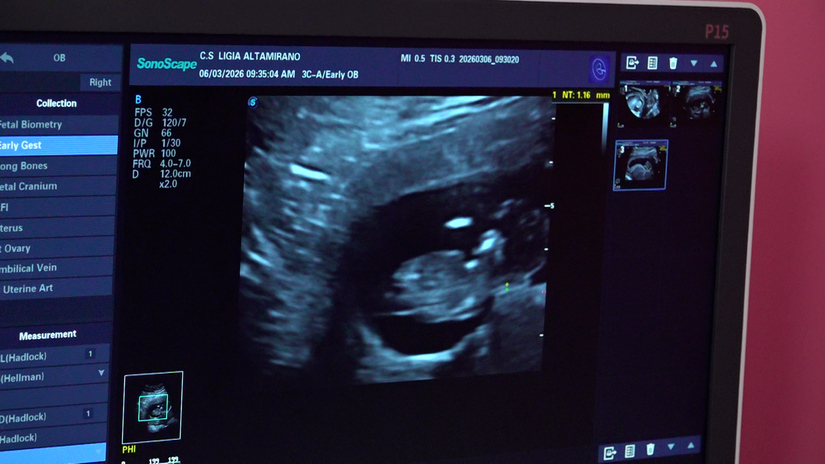

La doctora Judith García, directora del centro, comentó que a las mujeres se les realizan ultrasonidos para evaluar la edad gestacional y el riesgo de presentar alguna anomalía congénita, preeclampsia o embarazo pretérmino.

“Estamos realizando estudios a mujeres entre las 11 y 13 semanas de embarazo, con una evaluación completa de su gestación, con un ultrasonido específico de tamizaje, en el cual se evalúan entre 100 y 150 embarazadas, provenientes de todo el departamento de Managua y del Silais-Managua”.